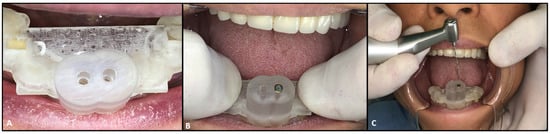

2. Case Report